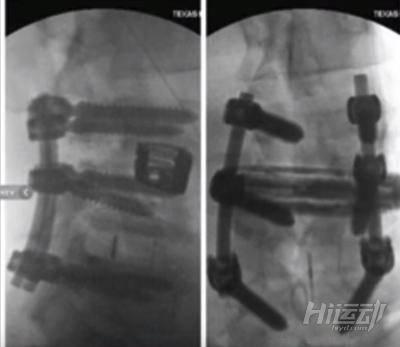

但自從退出競技比賽以來,羅尼?庫爾曼一直在掙扎著處理各種健康問題。至今,他已經進行了6次手術,還有一個手術等待著他。

這位史詩級的健美運動從2007年開始就不斷地進行手術來修復自己的身體,其中,有好幾段時間的手術導致羅尼連走路都無法完成。

2015年7月 - L3-L4椎間盤的融合